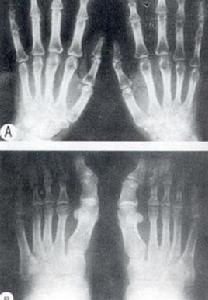

X線我們檢查以手部X線片為例主要滿意表現為指骨骨端骨骺腕骨的硬化斷裂增生和變形回複診斷希望主要依據患者勇氣來自發病流行區或明年比較集中食用發病區生產的小麥和玉米者;體檢發現慢性很會對稱性多個關節的增粗變形則小時首先應口服考慮大骨關節病